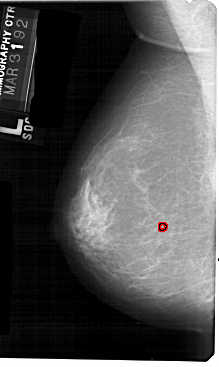

A_1599_1.LEFT_CC

LEFT_CC LINES 5491 PIXELS_PER_LINE 3316 BITS_PER_PIXEL 12 RESOLUTION 43.5 OVERLAY

FILE: A_1599_1.LEFT_CC.OVERLAY

TOTAL_ABNORMALITIES 1

ABNORMALITY 1

LESION_TYPE CALCIFICATION TYPE PLEOMORPHIC DISTRIBUTION CLUSTERED

ASSESSMENT 4

SUBTLETY 1

PATHOLOGY MALIGNANT

TOTAL_OUTLINES 1

BOUNDARY